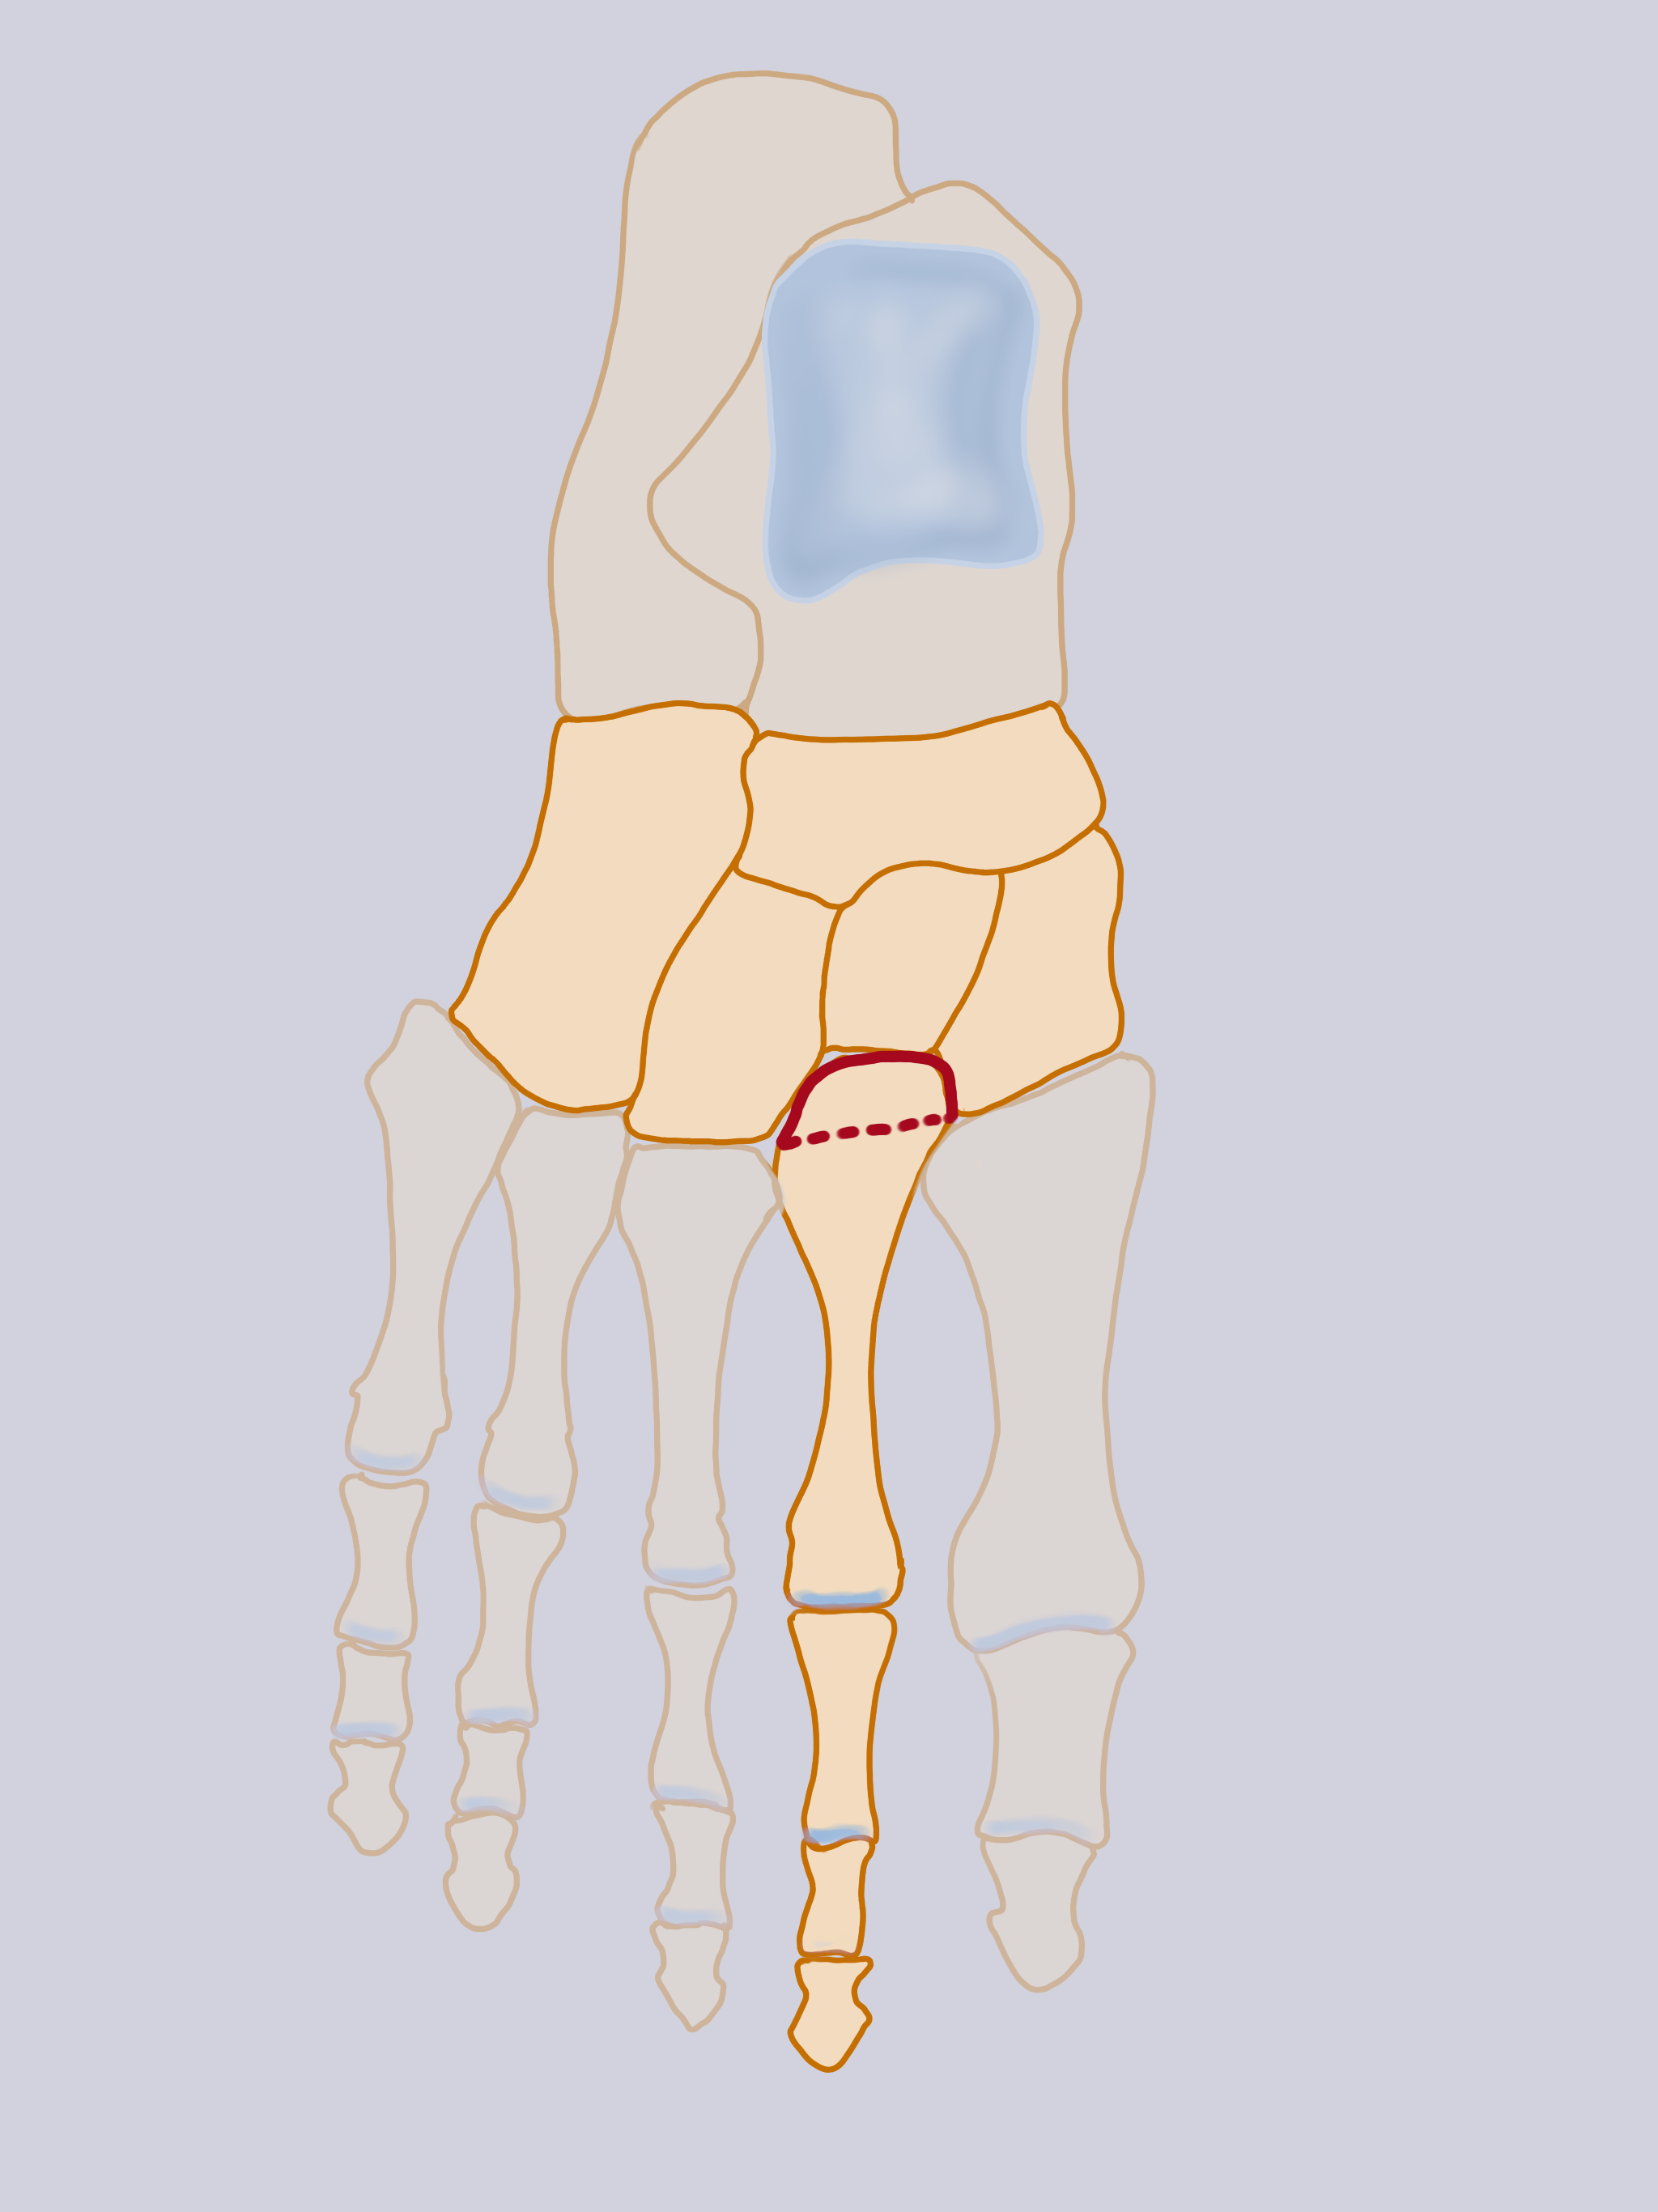

The tarsometatarsal joint (TMT) consists of the five metatarsals to the anterior tarsus, which is formed medially by the three cuneiform bones (C1, C2, C3) and laterally by the cuboid bone (Cu). The TMT joint consists of three synovial joints with three distinct capsules: medial (C1-M1), middle (C2C3-M2M3) and lateral (Cu-M4M5). (Fig 1) The metatarsals have a triangular base with a plantar apex, which favors dorsal dislocation (98%).

An appreciation of the functional anatomy of the complex set of bony and ligamentous structures forming this joint is imperative for the proper assessment and treatment of Lisfranc fracture-dislocations. This joint is characterized by a quasi-immobility of the middle compartment, in particular of the second metatarsal bone whose base is impacted between the cuneiform bones. This explaines, in case of dislocation force, the relative frequency of M2 base fractures (Fig 4).